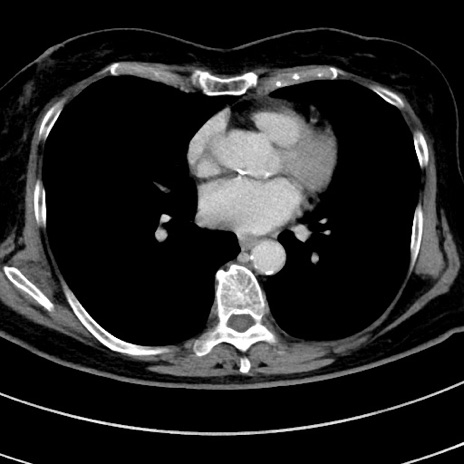

症例9(横断像)

【症例】 60歳代女性

【主訴】むかつき、みぞおちの痛み

【現病歴】3日前よりむかつきがあり、食事がとれない。

【既往歴】糖尿病

【身体所見】発熱なし、心窩部圧痛軽度あるも、腹膜刺激症状なし。

【データ】WBC 7400、CRP 1.92